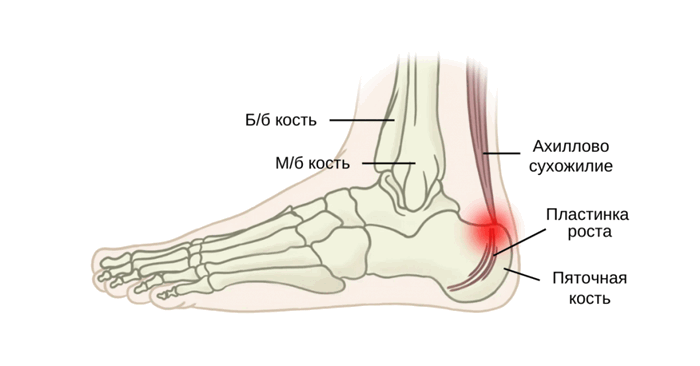

Клинически значимая анатомия

Пяточная кость расположена в задней, подошвенной области стопы. Ахиллово сухожилие прикрепляется внизу, сзади и примерно посередине пяточной кости. Плантарная фасция берет начало от медиального бугорка в подошвенной части пяточной кости. Ближе к эпифизу лежит апофиз, куда ахиллово сухожилие фактически и вплетается. Ростковая зона пяточной кости и ее апофиз испытывают большую нагрузку от плантарной фасции и ахилла. Кроме того, разница в темпе роста мышцы и кости может приводить к укорочению трицепса голени, в результате чего может снизиться амортизация между стопой и поверхностью опоры. Кроме того, у ахиллова сухожилия имеется довольно широкая область прикрепления, которая анатомически связана с плантарным апоневрозом. Фактически это помогает предотвратить травматические разрывы центра оссификации.

Болезнь Севера — это остеохондроз, вызванный слишком большими нагрузками на область прикрепления ахиллова сухожилия к пяточной кости и эпифизарную пластинку роста. Эта зона роста по форме напоминает букву «С» и может воспаляться из-за повторяющегося тракционного напряжения ахиллова сухожилия. Эпифизит пяточной кости часто поражает молодых спортсменов и, как считается, возникает из-за бега и прыжков.